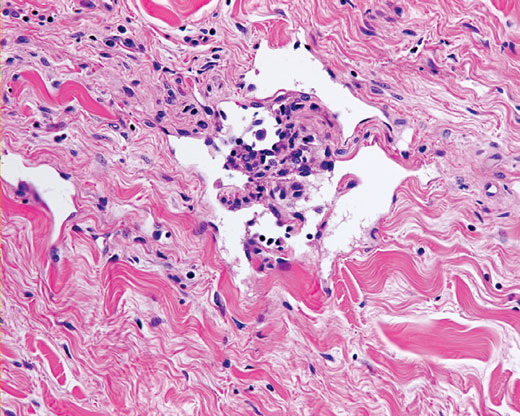

Atypical vascular proliferation =تكاثر وعائي لا نموذجي